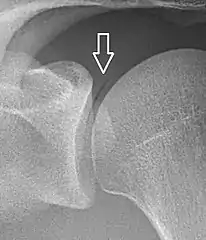

A vacuum sign, or vacuum phenomenon, is a normal finding on shoulder X-rays.